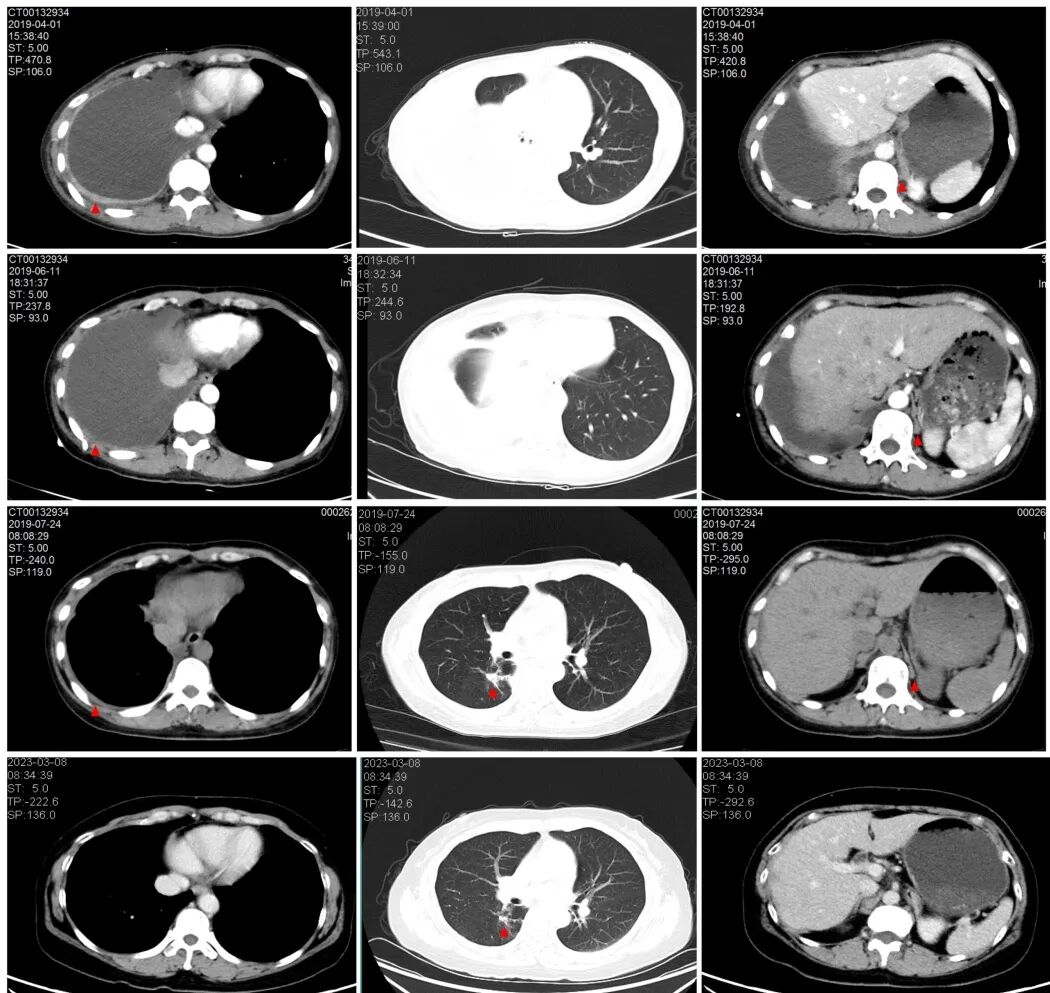

A(三代EGFR-TKI治疗前)CT提示右侧胸腔大量积液,右侧胸膜增厚,双侧肾上腺转移;

B (三代EGFR-TKI治疗后1月后)CT提示右侧仍大量胸腔积液,右胸膜、双肾上腺转移稳定;

C (三代EGFR-TKI联合节拍治疗1月后)右胸腔积液退缩,可见右肺小病灶,胸膜转移、双侧肾上腺转移逐渐退缩;

D(最后1次随访CT)右侧胸腔积液、右胸膜转移完全消失,右肺小病灶、双侧肾上腺转移少量残留。

2019年6月,张女士开始接受节拍治疗,令人惊喜的是,治疗1个月后,胸腔积液得到明显控制,胸膜转移、双侧肾上腺转移灶也逐渐退缩,治疗3个月后,胸膜转移、胸腔积液完全消失。现在,张女士仍在口服“三代EGFR-TKI联合节拍治疗”,该方案的无进展生存时间(PFS)已超过4年了,肿瘤接近完全缓解(CR),而且未发生任何治疗相关的副作用。